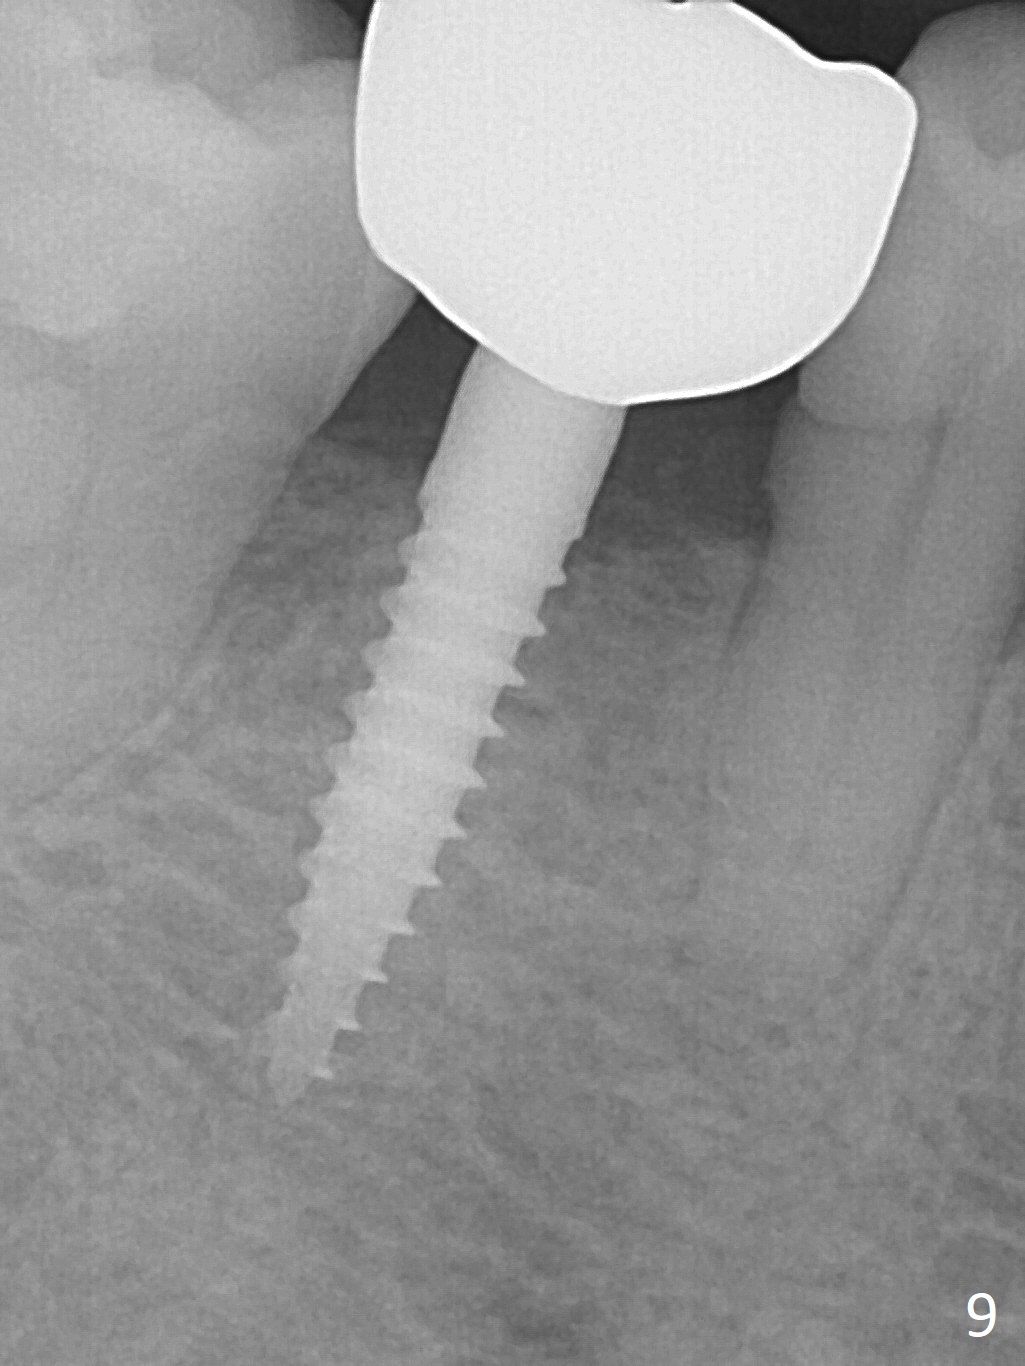

Before crown cementation, the ridge looks wider (Fig.7 *) than preop. There is no diastema between #31 and 32 (Fig.8, 17 days post cementation). The patient is pleased with less food impaction. The total treatment (including ortho) is 16 months. It appears that distalization of #29 is not effective to gain the bone width. In fact simultaneous GBR with implant placement is much more efficient. There is no bone loss 3 months post cementation (Fig.9). The gingiva looks healthy 10 months post cementation (Fig.10). The implant crown is functioning 1 year 9 months post cementation (Fig.11) and 3 years 7 months post cementation (Fig.12).